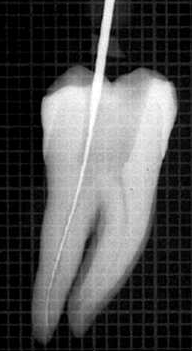

Se debe rectificar la cámara para que la lima acceda en forma vertical "A" para ello se utiliza la fresa SX  ó Pre RaCe

Acceso vertical con lima 10 manual